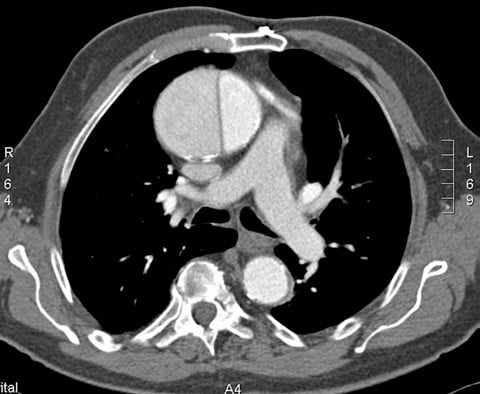

As the patient signed in, the registrar noticed he was sweating profusely, and she reported it to medical staff. The attending physician ordered routine blood work, which included a cardiac panel and a D-dimer test, as well as a computed tomography (CT) angiogram to rule out a pulmonary embolism (PE). The results of the D-dimer test were abnormally high (1500 mg/mL). The CT scan demonstrated a type A aortic dissection that began in the aortic root and extended into the aortic branch. The dissection continued into the descending aorta along the vertebrae. The patient was immediately transferred to another facility to undergo a heart operation.

Aortic dissections can be classified using 2 systems: Stanford and DeBakey. The Stanford classification system categorizes dissections according to whether they require surgical repair (type A) or can be managed using medications to control blood pressure (type B).1 Type A dissections affect the ascending aorta, whereas type B dissections do not (see Figures 1 and 2).2 The DeBakey system also categorizes dissections by required medical intervention; however, this classification system details the process, or origination, of the dissection and is divided into types I, II, and III. Type I dissections originate in the ascending aorta, likely continue through the aortic arch, and often involve the descending aorta or even the entire aorta.2 Type II dissections affect only the ascending aorta, while type III dissections solely affect the descending aorta (see Box ).2 The most common aortic dissections occur in the descending aorta.3